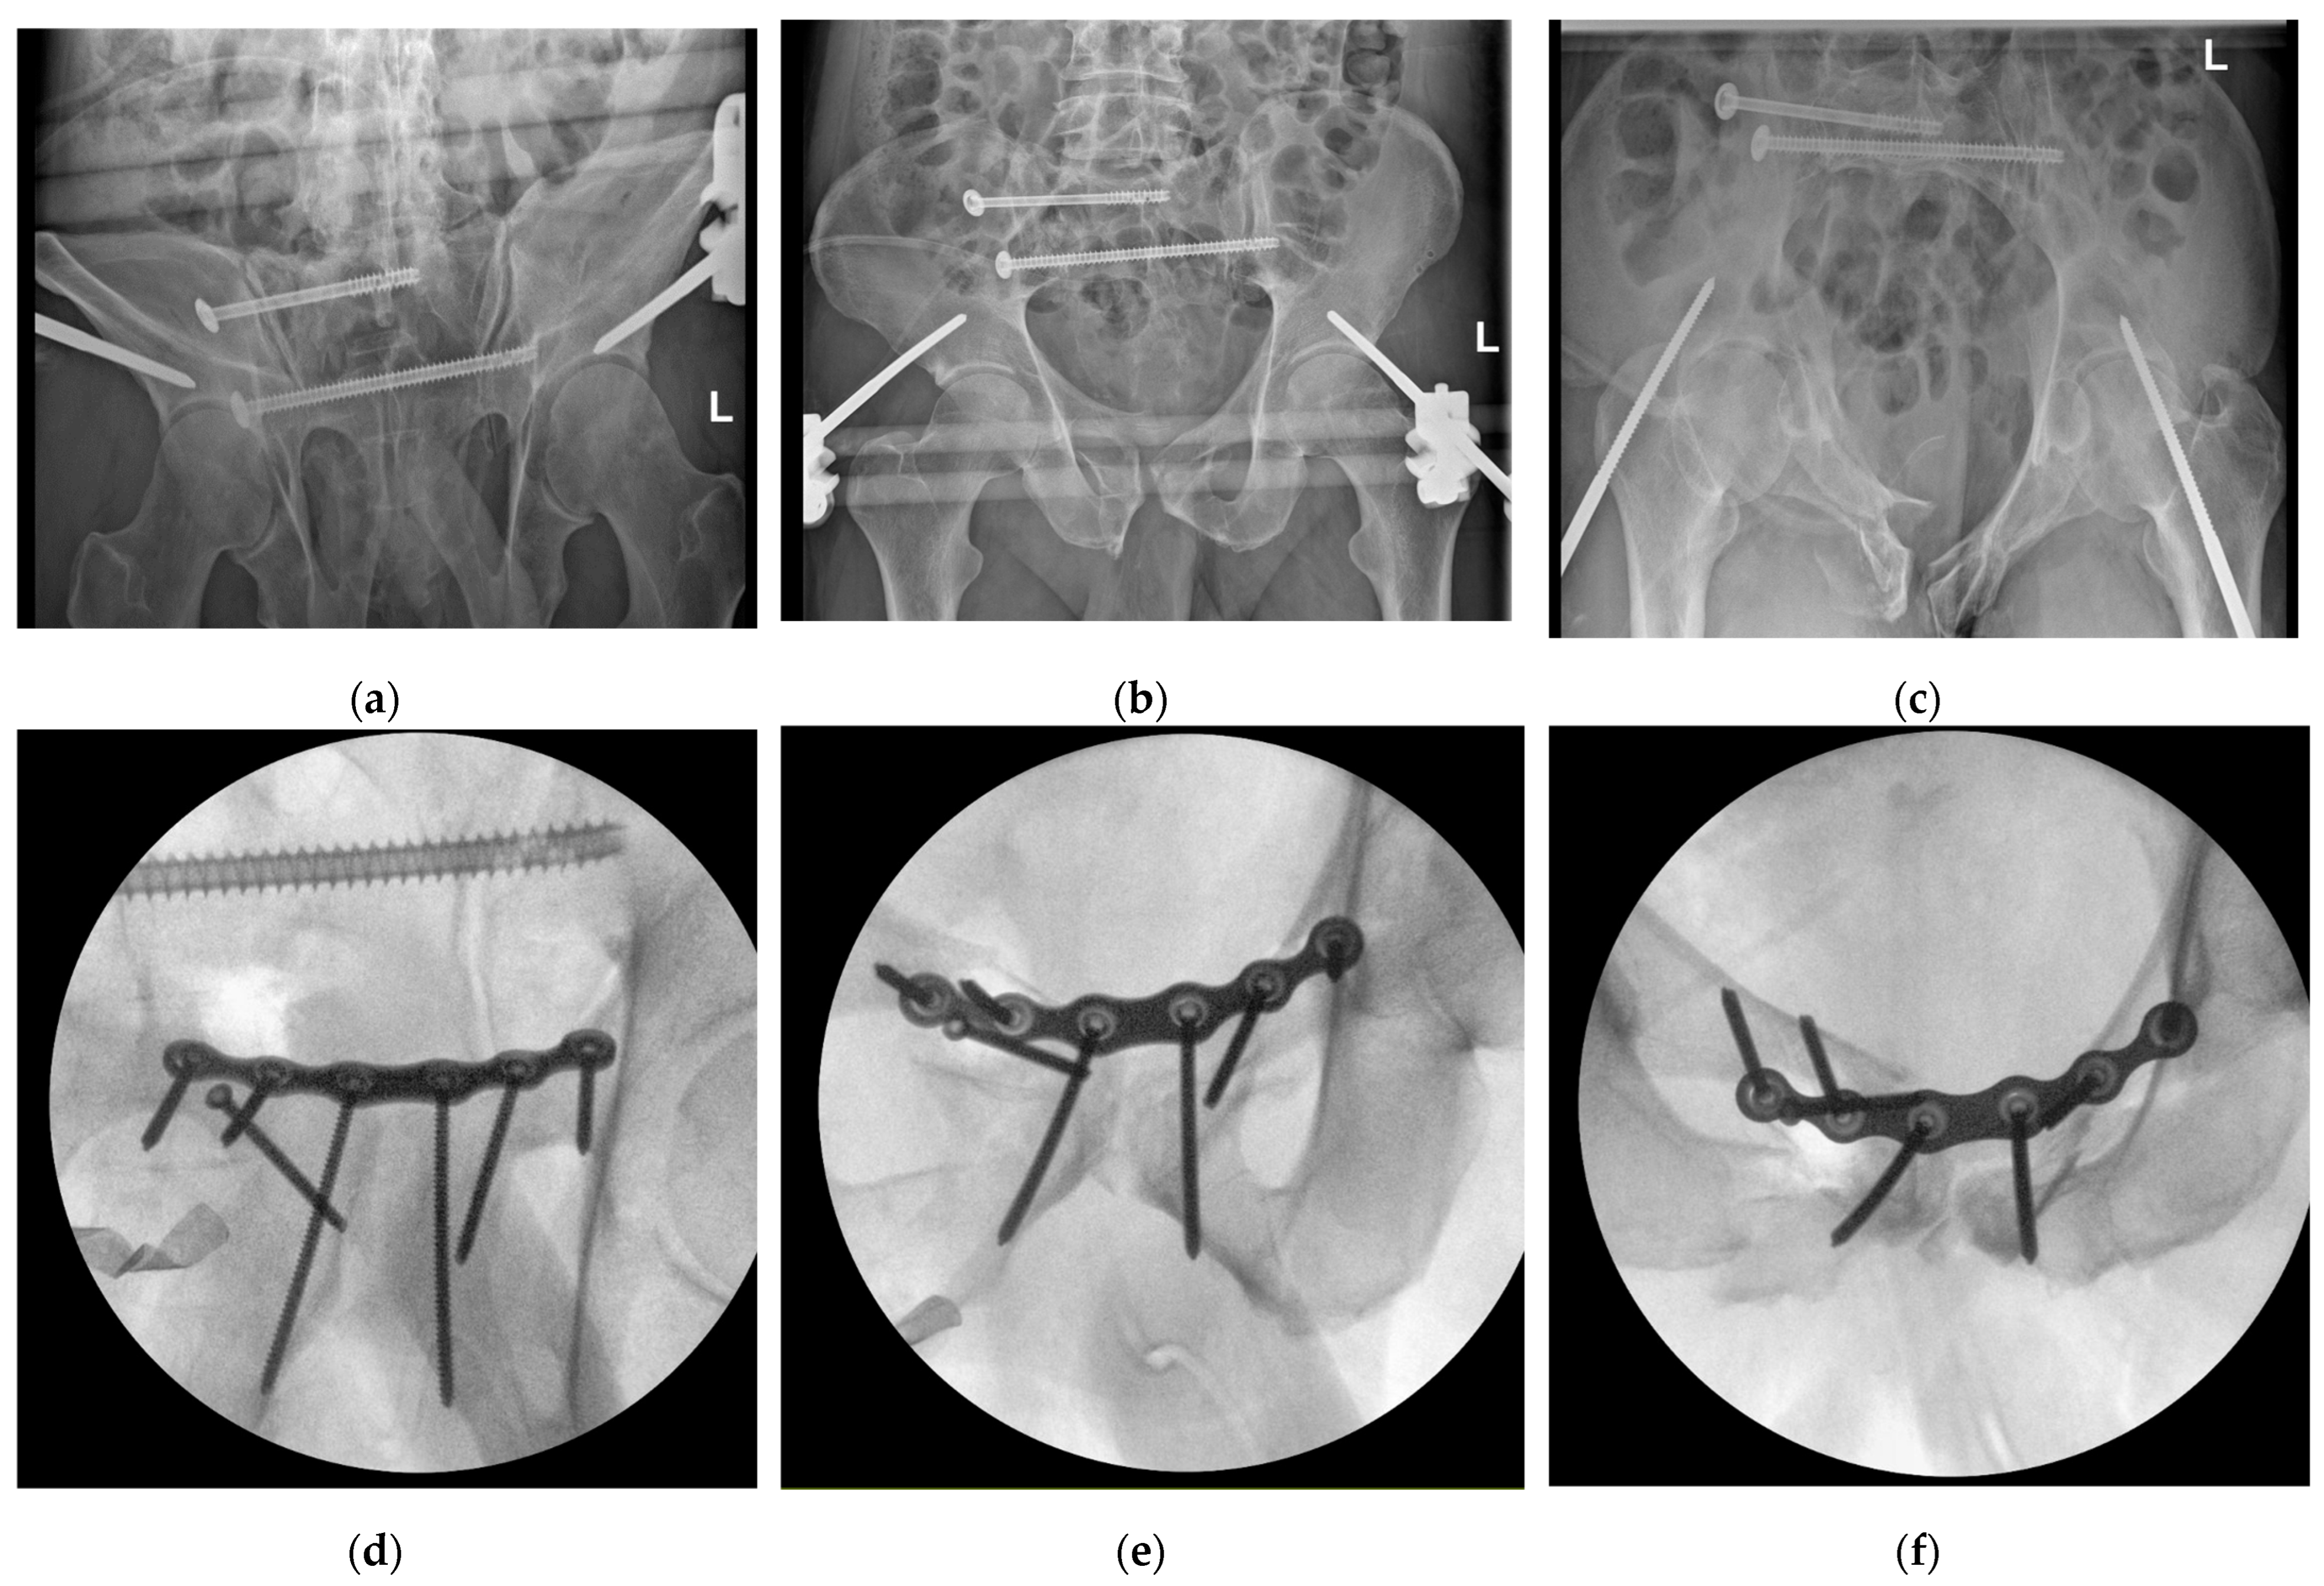

3.5. Fracture Repositioning and Osteosynthesis

3.6. Outcomes

4.3. Fracture Treatment